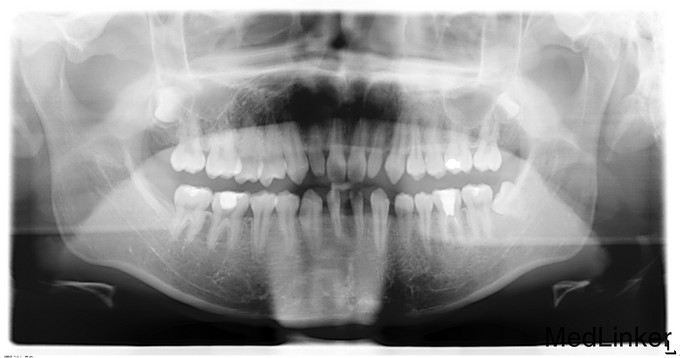

主诉:正畸科转诊咨询种植方案 现病史:患者先天缺失两下前牙,牙齿排列稀疏,遂至本院正畸科治疗,正畸科制定方案后转种植科咨询方案 既往史:无特殊

检查:下侧切牙双侧缺失,缺牙间隙约有1cm,其余无特殊 全景片示:下侧切牙双侧缺失